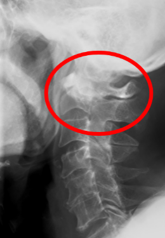

- 頸椎を横から見たレントゲン写真

まず、頸椎の不安定性の評価には単純X線が用いられます。神経障害を認めた場合、もしくは単純X線像で頸椎病変を疑った場合にはCTやMRIの適応となります。CTは骨びらんや脱臼、関節強直などの評価に有用です。脊髄や神経根の圧迫の有無の評価にはMRIが有用です。